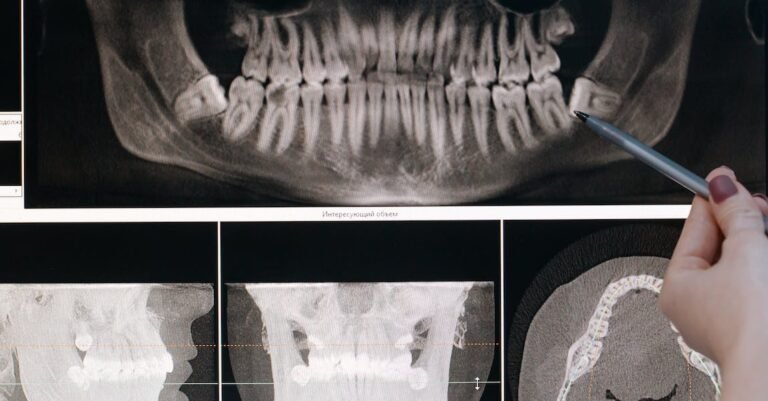

If you are considering a teeth whitening procedure, you should be aware that it only works on natural teeth. Artificial surfaces cannot be whitened by traditional whitening products. This applies to implants and crowns, as well as any type of fillings and veneers. When you whiten your teeth, these artificial surfaces will stay the same, while your natural teeth will be whitened.